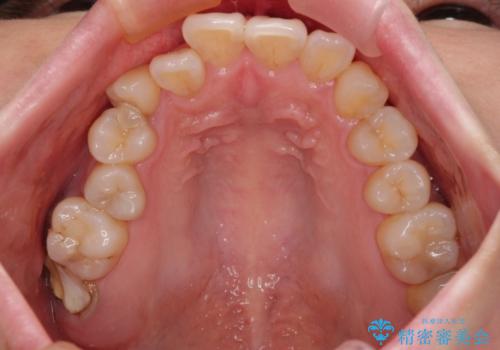

- 長年放置しているむし歯を気にして来院された患者様です。

外側を向いている上顎の奥歯は歯ブラシが十分に届かないため、むし歯となるケースが多いのですが、今回むし歯となってしまった歯がそれで、ボロボロになって根だけが残っている状態でした。

患者様と相談し、抜歯をした上でインプラントによる補綴治療を行うこととしました。